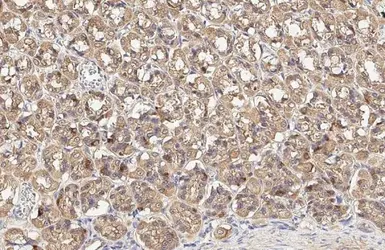

DRP1 antibody

Cat. No. GTX135364

ApplicationsWB IHC-P

ReactivityHuman, Mouse, Rat